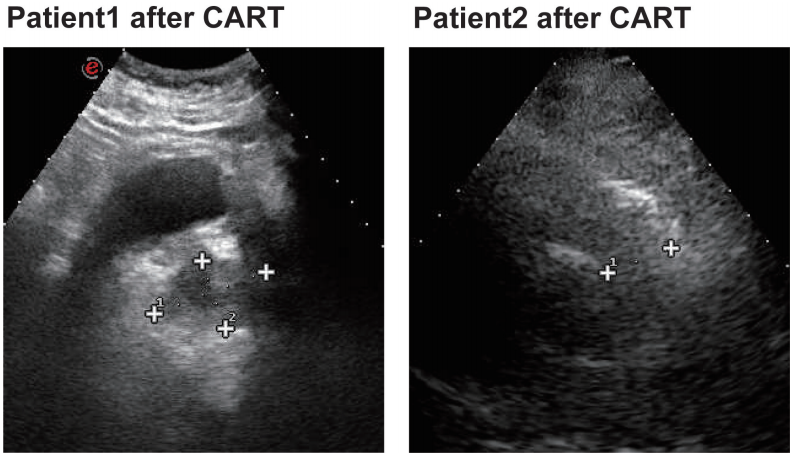

经过四次R-Gemox方案化疗后,患者于2018年4月进行了自体造血干细胞移植(HSCT)。随后的PET-CT(图1)显示甲状腺结节1.8*2.7*3.4 cm3,边界不清晰,SUVmax 16.38。建议患者接受CAR T治疗。2018年11月8日,进行氟达拉滨和环磷酰胺(FC)预处理方案以清除淋巴细胞,并于11月12日输注CAR T细胞。疾病在一个月时部分缓解,三个月时完全缓解。

图1. CAR T治疗前后两名患者的PET-CT图像

化疗结束2个月后淋巴结肿大,2018年8月再次进行淋巴结活检,提示生发中心起源的弥漫性大b细胞淋巴瘤和疾病进展。PET-CT(图1)提示化疗后淋巴瘤:右胸锁乳突肌和颈鞘深部、右颈根、左颈鞘、双侧锁骨上和下区域、纵隔胸腔入口和上纵隔血管间隙、两侧多个不同大小的腋窝深淋巴结FDG代谢不同程度增加。2018年9月19日采集外周血淋巴细胞。2018年9月29日,采用FC方案对淋巴细胞进行预处理清除,10月4日进行CAR T细胞输注。一个月后,病情评估为完全缓解。随访期间,患者TGAb、TMAb和TPOAb升高,但甲状腺功能正常。考虑继发性桥本甲状腺炎。